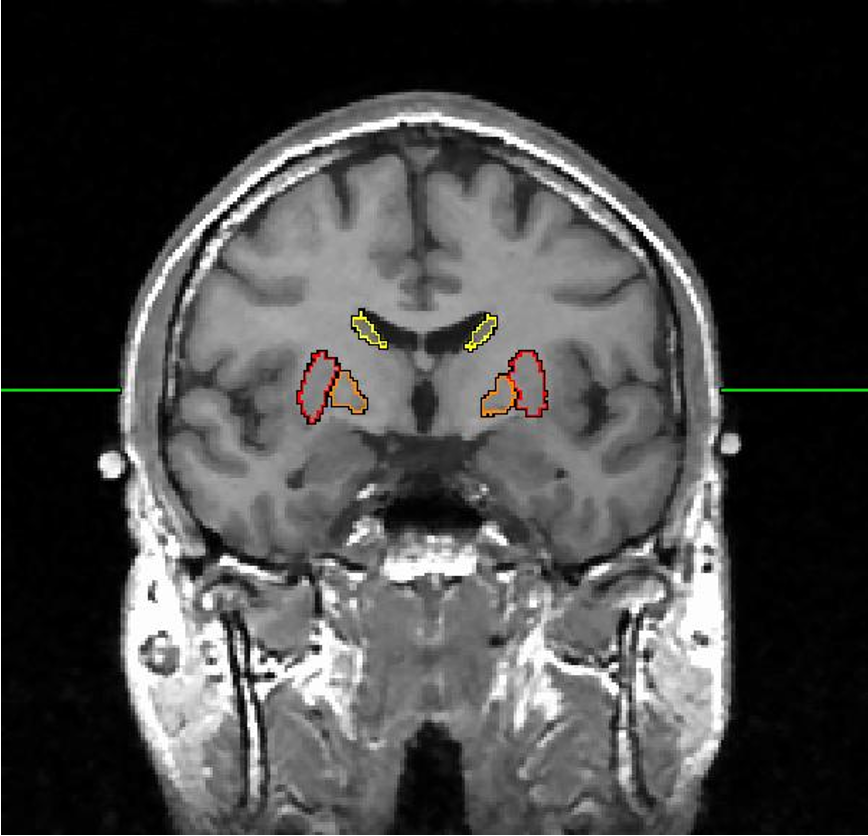

amygdala (almond)

hippocampus

hippocampus, amygdala, cingulate lobe

limbic system

includes cortex, basal ganglia (putamen, caudate nucleus, globus pallidus) & limbic system (hippocampus/ amygdala)

forebrain